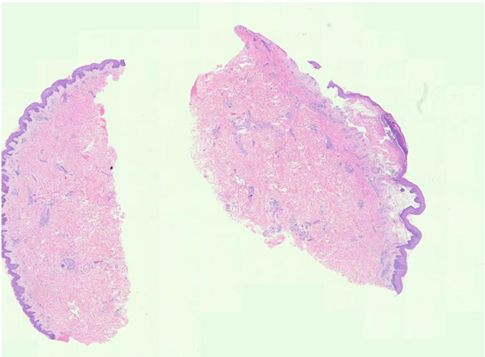

Figure 3: Histopathology showing: parakeratosis, acanthosis with neutrophilic infiltrationin the epidermis, and superficial perivascular lymphocytic infiltrates, including eosinophils in the dermis in consistance with Psoriasis (Left). while subepidermal blisters as a subcorneal cleft(split) accompanied by acantholytic keratinocytes within the granular layer parakeratosis containing eosinophils and lymphocytes infiltration, fibrin deposits and perivascular inflammation for BP(Right).